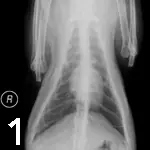

Laboratory Work. A CBC, biochemical profile, urinalysis, thyroxine measurement, and chest radiographs (Figures 1 and 2) were performed. Results of the CBC and biochemical profile were normal, with the exception of high-normal levels of BUN (38 mg/dl; reference range, 6 to 35 mg/dl) and creatinine (2.1 mg/dl; reference range, 0.4 to 1.9 mg/dl). Urinalysis revealed diluted urine (USG 1.019) but was otherwise unremarkable. Serum thyroxine concentration was normal.

Differential Diagnosis. Problems identified include respiratory distress characterized by increased effort and referred upper airway sounds, heart murmur, and anorexia. Differential diagnoses for respiratory distress include upper airway obstruction (including mass or laryngeal paralysis), pulmonary thromboembolism, hyperthyroidism, or other metabolic or systemic disturbances. This case is challenging due to the lack of radiographic abnormalities consistent with most common causes of feline respiratory distress.